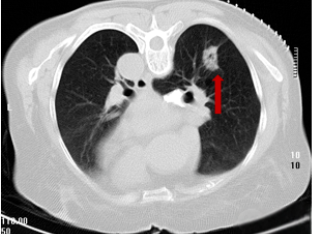

术后4月复查

术后1年复查